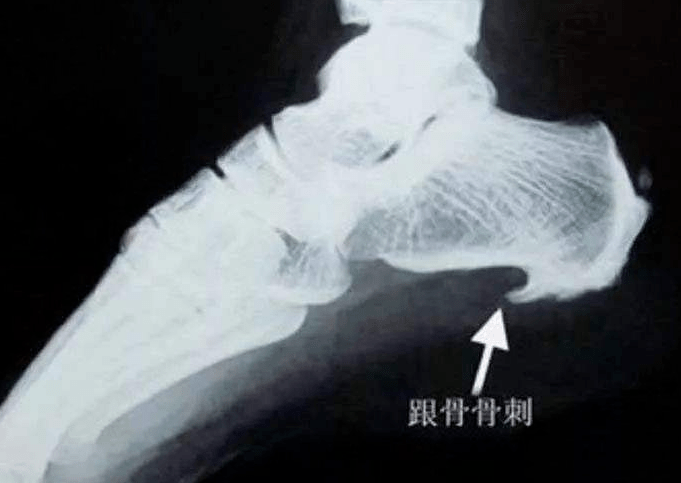

一图搞懂跟骨骨刺

比如最常见的,就是脚部跟骨上的骨刺.